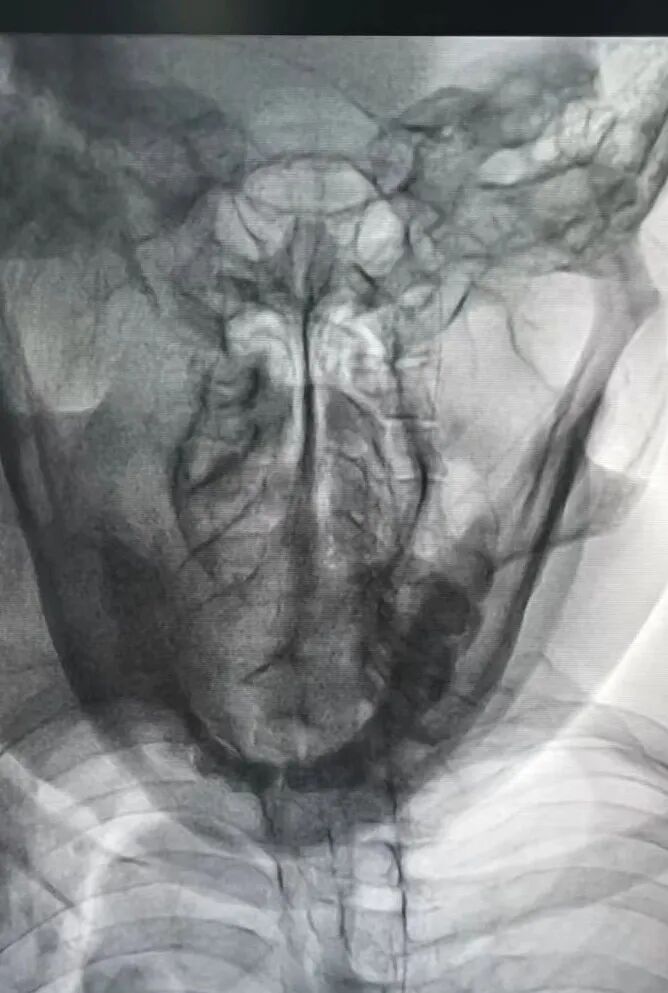

患者,杜某某,男,69岁,因腰臀部疼痛伴右下肢麻痛1年余入院,经多次治疗效果均不理想。该患者于2024年11月17日入住我院疼痛科,经完善腰椎核磁共振提示:腰椎L4-5、L5-S1椎间盘突出,突出物压迫以右侧L5-S1为主,对此疼痛科周理平主任带领他的团队对杜先生进行了右侧腰4腰5及腰5骶1腰椎间盘射频消融术+经皮腰5-S1椎间盘胶原酶化学溶解术,术后杜先生自觉疼痛明显消失。

图片